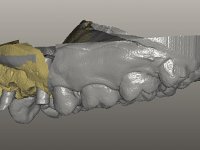

O paciente foi observado conjuntamente e a dúvida que surgiu de imediato foi se seria possível com a regeneração óssea a efectuar poder ser reabilitada naturalmente a zona das papilas interdentárias. Nesse sentido foi feito um enceramento de diagnóstico que contemplaria as duas hipóteses, utilizando ou não a cerâmica gengival. A confecção desse enceramento foi fundamental para expor ao paciente a dificuldade da reabilitação. O wax-up deu origem a um mock-up que foi aprovado pelo paciente e que simultaneamente serviu de guia imagiológica. O caso foi planificado cirurgicamente e realizada uma guia cirúrgica com que foram colocados os implantes. Após 10 semanas foi feita a 1ª impressão para confecção da ponte provisória. Foram criados os primeiros perfis de emergência na gengiva artificial e foi digitalizado o modelo. Por processo de CAD-CAM foi confeccionada uma ponte provisória aparafusada baseada no enceramento de diagnóstico. A ponte trabalhou durante 8 semanas os tecidos moles que foram fielmente copiados numa impressão com técnica de moldeira aberta. Os transferes foram individualizados com resina composta para copiarem fielmente os perfis de emergência criados pela ponte provisória. Confeccionado o modelo de trabalho definitivo, foi realizada uma infra-estrutura em zircónio seguindo a orientação do enceramento de diagnóstico. O assentamento da infra-estrutura foi testado em boca e simultaneamente foi novamente impressionados os tecidos moles com um silicone fluido. Nessa consulta foi feito o levantamento da cor. Os dentes 13 e 23 apresentavam uma saturação anormalmente forte que resolvemos não valorizar, optando por privilegiar a relação com o sector antero-inferior. Foi realizada uma nova gengiva artificial com a impressão que acompanhou a impressão de arrasto com a infra-estrutura. Após a colocação da cerâmica na infra-estrutura foram coladas as meso-estruturas. O trabalho final foi aparafusado lentamente permitindo a adaptação dos tecidos moles.